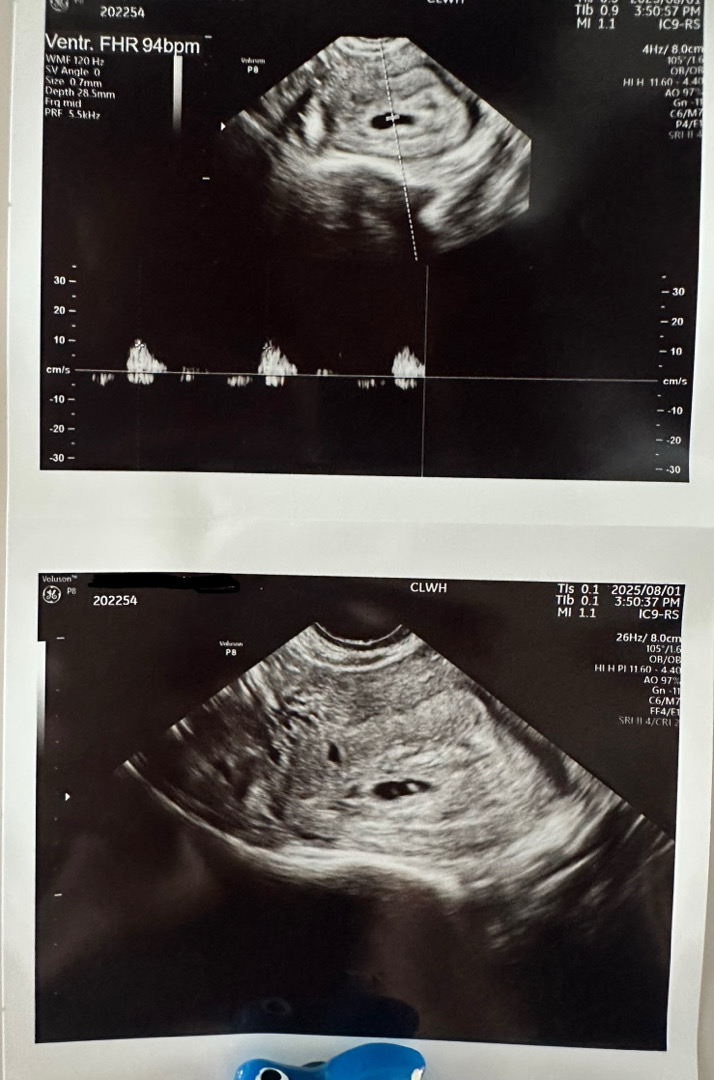

자임 6주 3일인데 심소 94bpm이에요 아직 6주 초기라 몇일 후면 더 잘들릴꺼라고 일주일 후에 보자구 하시긴 했는데 걱정핑인 저는 계속 검색만 하구 있네요ㅠ 혹시 다른분들은 어떠셨나요..?